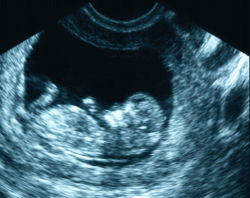

May 26, 2015 (Sacramento) – The California Assembly has passed a controversial measure, Assembly Bill 775, that would require crisis pregnancy centers to disclose if they have no licensed medical provider on staff and to provide women with a list of options including public programs offering free or low-cost prenatal care for those wishing to carry pregnancies to term and abortions for those who don’t.